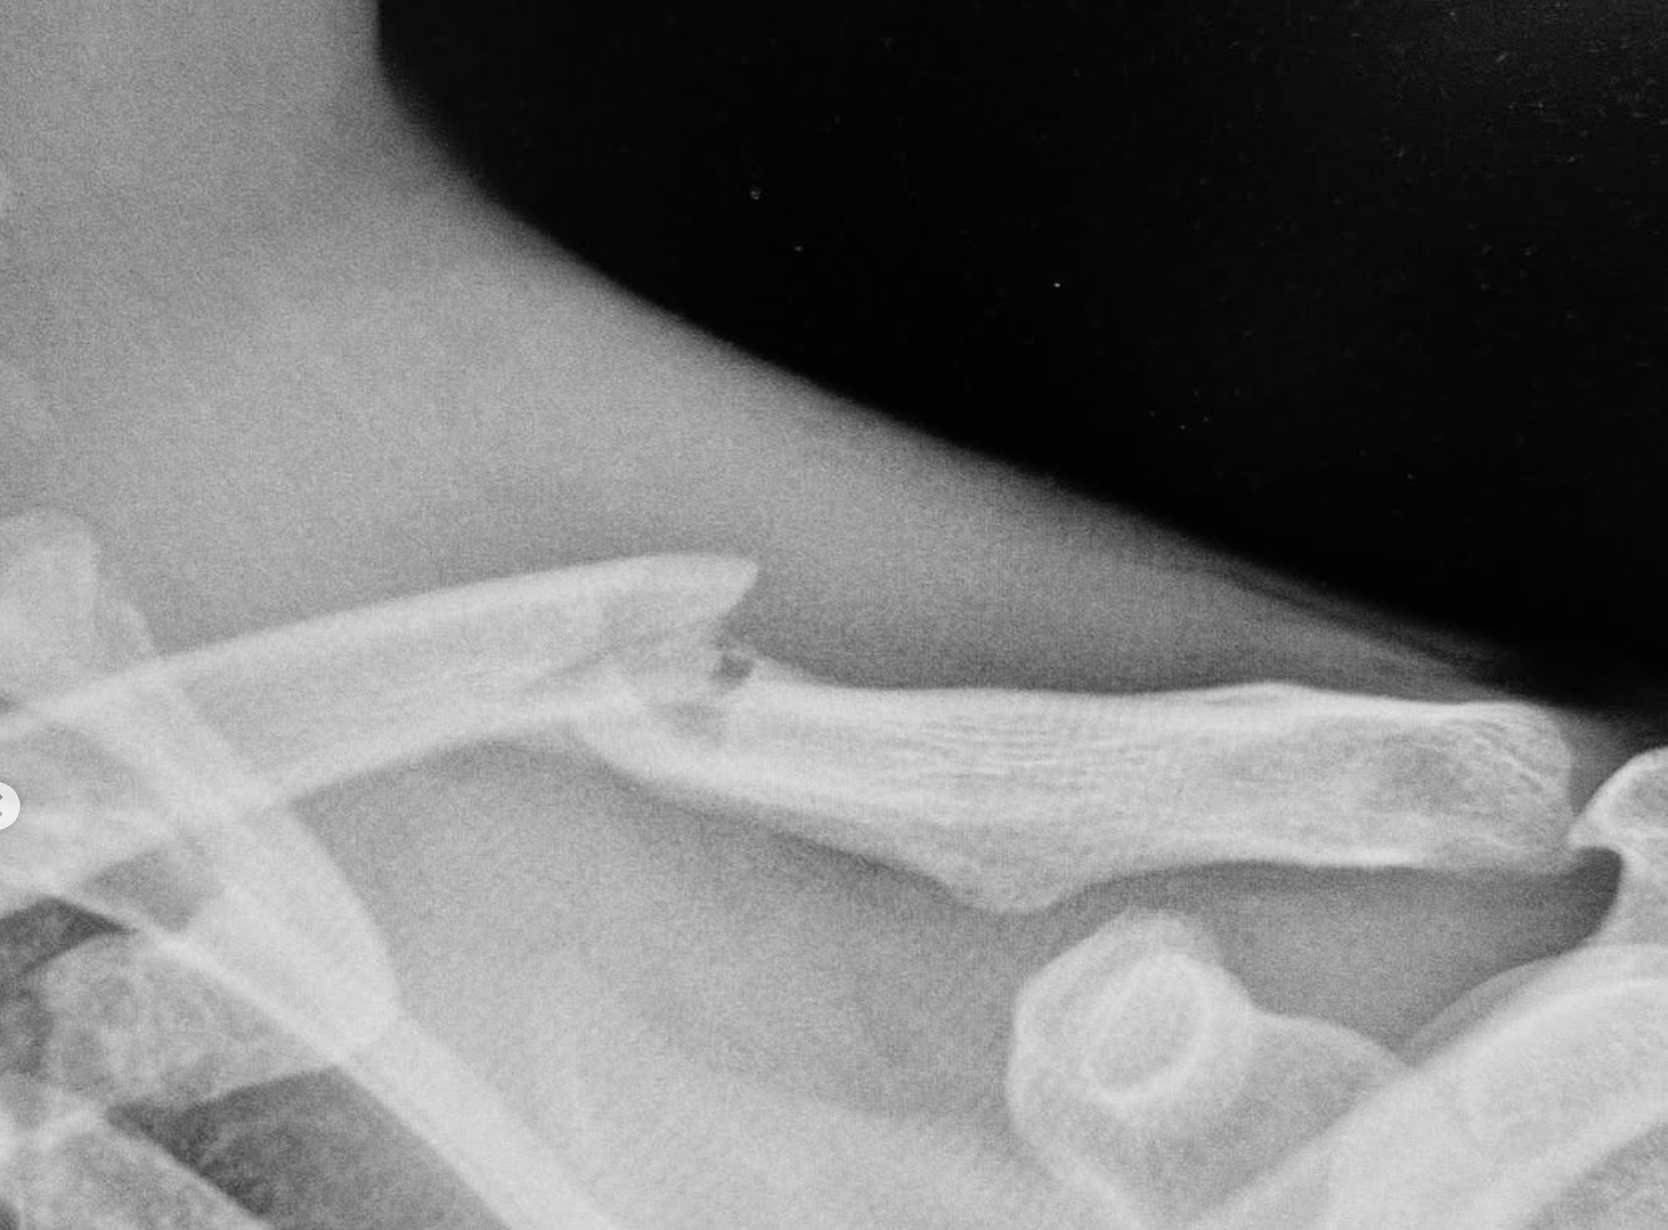

Emil Johansson erneut verletzt – Gebrochenes Schlüsselbein und Rippen nach Sturz beim Crankworx Cairns Slopestyle 25

Der schwedische Slopestyle-Star Emil Johansson hat sich bei einem Sturz während des Crankworx Cairns Slopestyle-Wettbewerbs das Schlüsselbein und eine Rippe gebrochen. Der Vorfall ereignete sich während seines ersten Laufs, als er bei der Landung eines Tricks die Kontrolle verlor und hart auf dem Boden aufschlug. Trotz des schmerzhaften Sturzes stand Johansson zunächst wieder auf, musste jedoch medizinisch versorgt werden und konnte nicht zum zweiten Lauf antreten.

Emil Johansson injury Cairns 2025​

Die medizinische Prognose für Schlüsselbeinbrüche liegt in der Regel bei einer Heilungsdauer von mindestens sechs Wochen, wobei die vollständige Rückkehr zur Wettkampfform oft länger dauert. Es bleibt abzuwarten, wie sich Johanssons Verletzung auf seine Teilnahme an den kommenden Veranstaltungen der Crankworx World Tour auswirken wird.